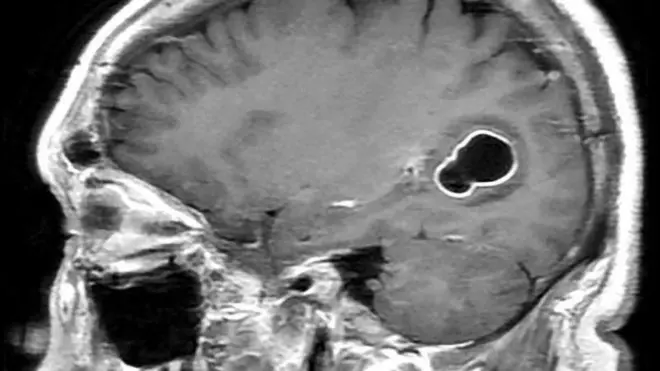

Ragga doonaya inay caruur dhalaan marka da’doodu gaarto 35 sano waxay leeyihiin khatar sare oo ah in ilmahoodu ku dhashaan miisaan yar, qalal, ama u baahandan hawo farsamo ah si uu u neefsado isla dhalashada ka dib.

Dadka da'doodu ka weyn tahay 45 sano waxay 14% aad ugu dhowdahay inay dhalaan ilmo dhicis ah halka kuwa ka weyn 50 ay leeyihiin 28% khatarta sare ee dhallaanka u baahan inuu waqti ku qaato qaybta daryeelka degdegga ah.

Qoraaga cilmi-baaristan Michael Eisenberg, oo ah borofisar ku takhasusay urology ayaa caddeeyay in tirooyinkaas aan loo fasirin qaylo-dhaan. Ra'yigiisa, natiijadu waxay caawisaa qoysaska inay si wanaagsan u qorsheeyaan oo ay ula socdaan hadba sida loo baahdo.

"Waxaa jira u janjeera in la eego arrimaha hooyada marka la qiimeynayo khatarta la xiriirta dhalashada. Laakiin daraasaddeenu waxay muujineysaa in dhalmada cunugga caafimaad qaba ay tahay dadaal kooxeed, da'da aabaha ayaa sidoo kale wax ku biirisa," ayuu yiri Michael Eisenberg.

Cilmi-baariyso kale oo soo baxay sanadkii 2017-kii ayaa arrintan si isku mid ah u dhigay taas oo tilmaamay khatar sii kordhaysa ee la xiriirta waalidka da’ada weyn ee cudurka autism ee ilmaha.

Sidaas oo kale cilmi-baadhistu waxay tilmaantay in 10-kii sannadoodba mar ay korodho da’da aabuhu, ay 21% ka badan tahay suurtogalnimada in ilmuhu ku dhaco xanuunkan, kaas oo la xidhiidha dhibaatooyinka xagga xidhiidhka, is-dhexgalka bulshada iyo hab-dhaqanka.